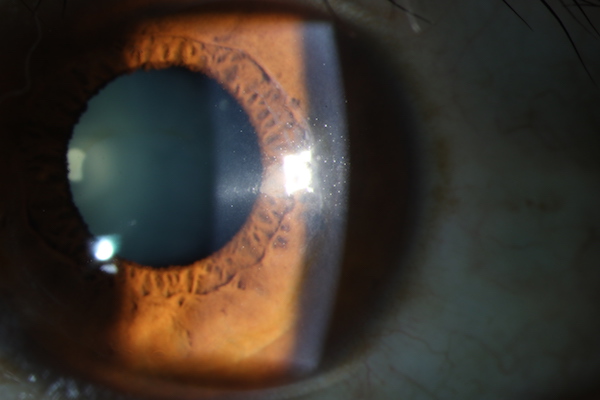

术后2年,患者角膜透明

2015年,李美燕博士在周行涛教授指导下,原创性地把远视透镜植入一个濒临角膜移植的圆锥角膜患者的角膜层间,经随访至术后2年,患者的裸眼视力从术前的0.1提高到术后的0.3、框架眼镜矫正视力从术前0.3提高到术后0.5,近视从术前的1350度下降到术后325度,散光从术前600度下降到150度。这是国际上首次将新鲜远视透镜移植治疗圆锥角膜的成功病例;该技术在改善屈光度(视力)的同时,也加厚了角膜,避免了角膜移植,并具有潜在加固角膜,提高角膜生物力学的良好作用。